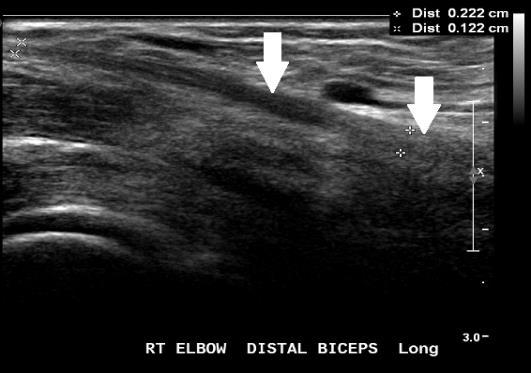

Fig. 1 Ultrasound showing a normal distal biceps tendon inserting at the radial tuberosity.

Ultrasound

Can confirm the tendon rupture and locate the tendon remnant

Fluid or haematoma may be seen in a measurable tendon gap

On ultrasound the very distal attachment to the tuberosity may be difficult to visualise due to the oblique tendon path. Determining the grade of

distal partial tears can be more difficult in muscular patients

Ultrasound is operator dependent and most useful when performed by experienced sonographers and radiologists

Fig. 2 Ultrasound showing normal biceps tendon (white arrows). Fig. 3 Ultrasound: The distal biceps tendon is ruptured. There is fluid and haematoma at the tendon defect (red arrow), and the tendon is retracted proximally (white arrow).